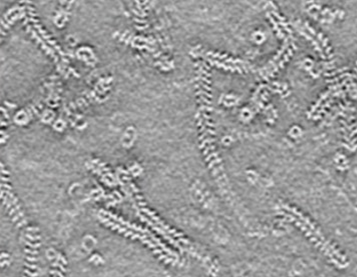

Pneumoviridae Table of Contents Book: Pneumoviridae Family: Pneumoviridae Genus: Metapneumovirus Genus: Orthopneumovirus Authors: Pneumoviridae Citation: Pneumoviridae Further reading: Pneumoviridae References: Pneumoviridae Resources: Pneumoviridae Species List: Pneumoviridae Family: Pneumoviridae Read more Genus: Metapneumovirus Read more Genus: Orthopneumovirus Read more Authors: Pneumoviridae Read more Citation: Pneumoviridae Read more Further reading: Pneumoviridae Read more References: Pneumoviridae Read more Resources: Pneumoviridae Read more Species List: Pneumoviridae Read more